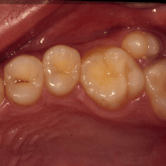

Caries dental

La caries dental es la descomposición del esmalte y la dentina del diente causada por ácidos producidos por bacterias en la placa dental. En los niños, las caries son especialmente comunes debido a una dieta rica en azúcares y una higiene bucal insuficiente.

Los padres suelen notar manchas blancas o marrones en los dientes de sus hijos, dolor al comer alimentos dulces o fríos, y a veces, cavidades visibles.

Es crucial tratar las caries temprano para evitar problemas más graves y mantener la salud dental de los niños